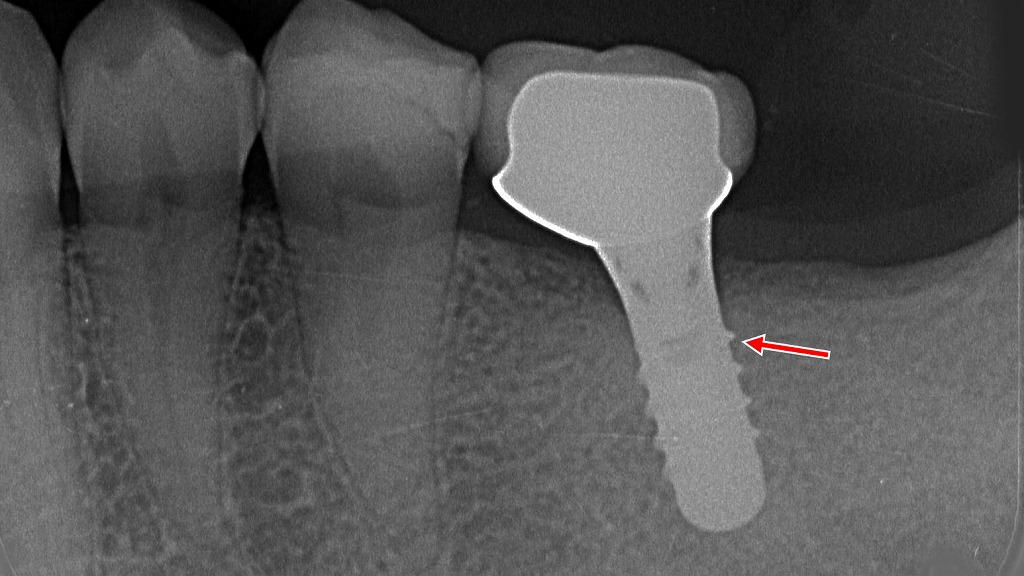

インプラントによる噛む力の回復

歯の欠損を放置すると、噛む力の低下や咀嚼効率の悪化が進み、口腔機能低下症の一因となります。

レントゲン画像の矢印部は、欠損部にインプラントを埋入し、咀嚼機能を回復した症例です。

インプラントは顎の骨に直接固定されるため、しっかり噛める力を取り戻しやすく、食事・発音・嚥下といった口腔機能全体の維持・改善に有効な治療選択肢の一つです。